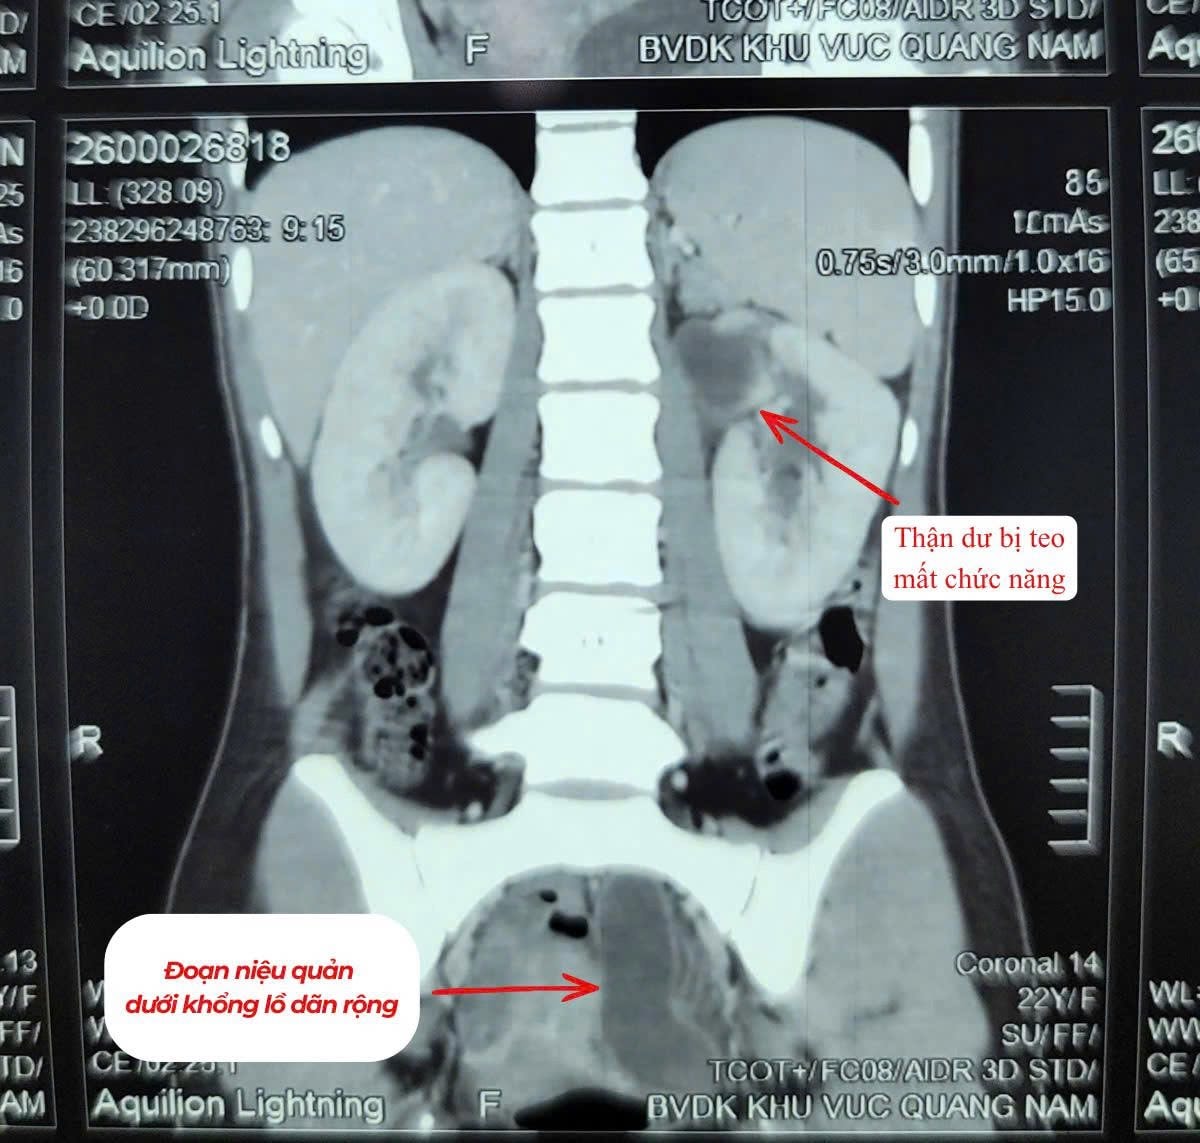

Qua thăm khám và thực hiện các cận lâm sàng cần thiết, các bác sĩ chẩn đoán bệnh nhân có dị tật thận – niệu quản đôi bên trái, trong đó một thận bị mất chức năng, niệu quản giãn to bất thường, ứ nhiều mủ gây nhiễm trùng nặng.

Bệnh nhân có quả thận thứ 3 mất chức năng, niệu quản giãn to bất thường, chứa nhiều mủ gây nhiễm trùng. Ảnh: BVCC